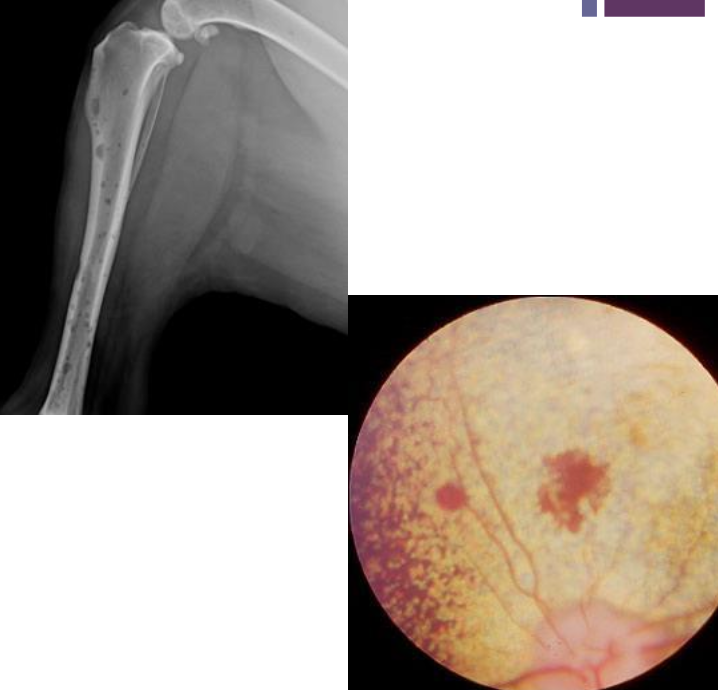

How can radiographic bone lesions appear?

Can be isolated, discrete lesions or diffuse osteopenia

Common sites have active hematopoiesis → vertebrae, ribs, skull, proximal and distal long bones

radiographic bone lesions

2. lytic bone lesions

fundoscopic exam

bony lesions, pathologic fracture